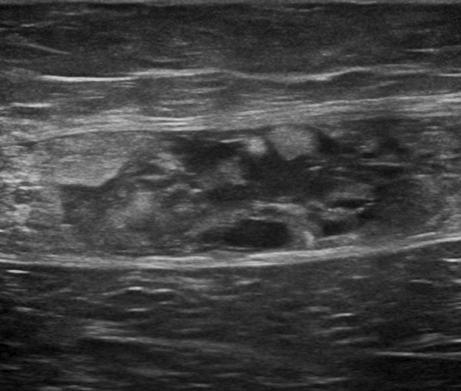

Chấn thương thành bụng - Ảnh 2

Chấn thương thành bụng

» Thông tin: Nam giới – 50 tuổi.

» Lâm sàng: Chấn thương thành bụng.

# Đụng dập, tụ máu cơ thành bụng.